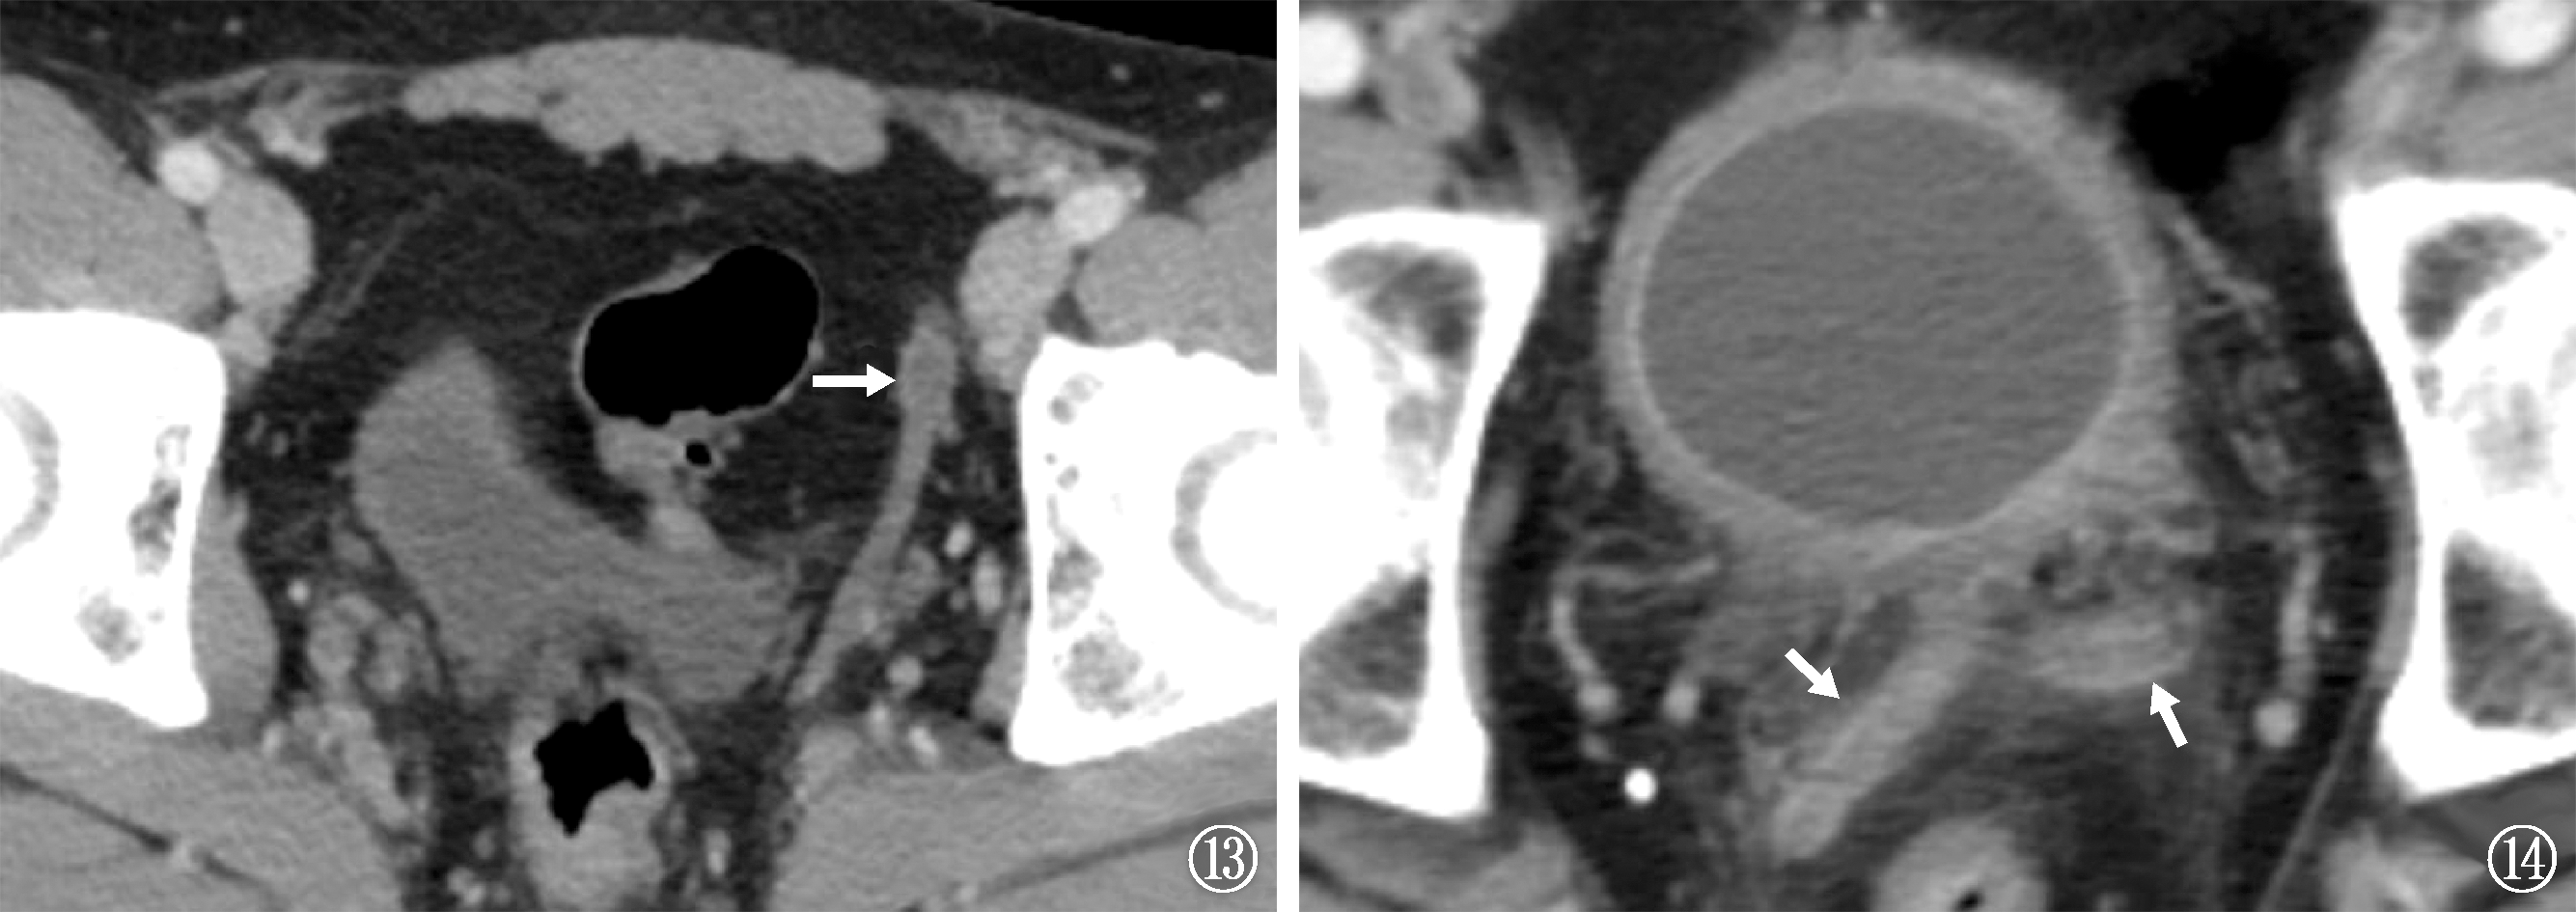

男性生殖系统结核(male genital tuberculosis,MGTB)可发生在男性生殖系统的各个器官,MGTB临床症状不典型或无临床症状,容易造成漏诊和误诊,随着医学影像学技术的发展,影像学表现在MGTB的诊断和鉴别诊断中有着重要的作用。作者旨在系统归纳男性生殖系统各个器官结核的超声、计算机断层扫描(computed tomography,CT)和磁共振成像(magnetic resonance imaging,MRI)的表现,提高对MGTB的认识和临床诊断能力。

| [10] | Fu X, Bi Y, Qi M, et al. Computed tomography imaging analysis of hematogenous disseminated pulmonary tuberculosis cases combined with prostate tuberculosis. BMC Med Imaging, 2025, 25(1):212. doi:10.1186/s12880-025-01753-7. |

| [40] | Baral S, Chhetri RK, Gyawali M, et al. Prostate tuberculosis complicated by huge prostatic abscess: A rare case report from Nepal. Int J Surg Case Rep, 2020, 77:152-156. doi:10.1016/j.ijscr.2020.10.045. |

| [41] | Yang G, Ruan L. Imaging findings of prostate tuberculosis by transrectal contrast-enhanced ultrasound and comparison with 2D ultrasound and pathology. Br J Radiol, 2022, 95(1129):20210713. doi:10.1259/bjr.20210713. |

| [42] | Li Y, Dan S, Yang F, et al. Prostate tuberculosis mimicking prostate cancer: Case report and literature review. Medicine (Baltimore), 2023, 102(47):e36172. doi:10.1097/MD.0000000000036172. |

| [43] |

Joshi PV, Shewalkar B, George T, et al. The Great Mimicker-Tuberculosis Involving Prostate and Vertebrae Posing as Metastatic Prostate Carcinoma on FDG PET/CT. Clin Nucl Med, 2020, 45(3):206-208. doi:10.1097/RLU.0000000000002789.

URL pmid: 31652162 |

| [44] |

Cheng Y, Huang L, Zhang X, et al. Multiparametric Magnetic Resonance Imaging Characteristics of Prostate Tuberculosis. Korean J Radiol, 2015, 16(4):846-852. doi:10.3348/kjr.2015.16.4.846.

URL pmid: 26175584 |

| [45] | Bour L, Schull A, Delongchamps N, et al. Multiparametric MRI features of granulomatous prostatitis and tubercular prostate abscess. Diagn Interv Imaging, 2013, 94(1):84-90. doi:10.1016/j.diii.2012.09.001. |

| [46] | 王向东, 王亚丽, 高跃丽. 前列腺结核的磁共振弥散加权成像及超声表现. 新发传染病电子杂志, 2020, 5(3):188-190. doi:10.19871/j.cnki.xfcrbzz.2020.03.010. |